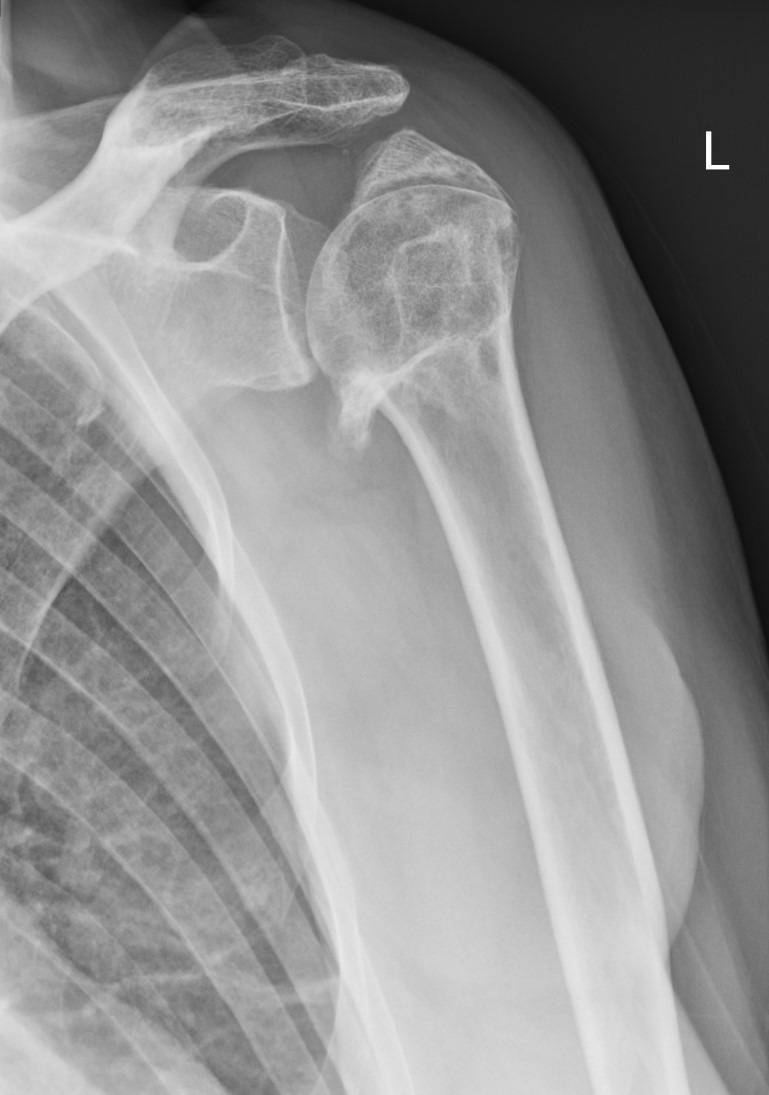

Ved den initiale vurderingen tas det rutinemessig vanlig røntgenbilde i to plan med projeksjonene «sann front» (glenohumeralleddet friprojisert) og scapula-Y-bilde (90 grader på sann front). CT-undersøkelse skal alltid tas hvis operasjon vurderes. MR-undersøkelse har ingen plass i diagnostikk og vurdering av en akutt proksimal humerusfraktur. Det kan iblant være nyttig i utredning av følgetilstander (senere enn 3–6 måneder), men det krever samarbeid med en erfaren skjelettradiolog for tolkning av relevante funn.

Det finnes mange ulike bruddklassifikasjoner for proksimal humerusfraktur. De to vanligste klassifikasjonene er fra AO Foundation / Orthopaedic Trauma Association (AO/OTA), sist oppdatert i 2018, eller Neer (9, 10). Med utgangspunkt i AO/OTA-klassifikasjonen kan man dele inn i 2-, 3- og 4-parts frakturer, som vist i figur 1. Det er praktisk og prognostisk viktig om caput er frakturert langs collum anatomicum (type C-brudd) eller om hoveddelen av bruddlinjen ikke engasjerer denne (type A- og B-brudd). Dette har sammenheng med blodtilførselen til caput og høy risiko for avaskulær caputnekrose ved type C-brudd.

Videre er endring fra anatomisk inklinasjon (aksen normalt på collum anatomicum-planet) av betydning: Valgus med caput stuket ned mot lateralt, eller varus med caput dislokert medialt. Caput kan også ofte innta posteriør feilstilling i sideplanet. Røntgenbildet kan gi informasjon om både bruddstabilitet og prognose.

Vanlige grenseverdier for å vurdere kirurgisk behandling hos eldre er caput med varusfeil på > 30 grader (mest alvorlig) eller valgusfeil eller posteriør vinkelfeil på > 45 grader (11). Dessuten vurderes graden av kontakt mellom hovedfragmentene. Hos yngre er toleransegrensen for feilstilling noe lavere, og feilstilling av tuberklene vektlegges mer. En CT-undersøkelse av skulderen med fremstillinger i tre plan (3D) gir tilleggsinformasjon dersom man er i tvil om tolkningen av vanlige røntgenbilder.